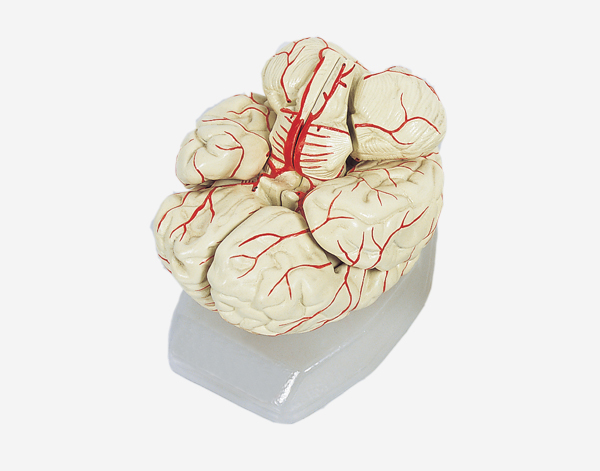

Human Brain With Arteries

Model of Human Brain With Arteries

This model facilitates the medical students to get a correct understanding of the external features of the brain and its arte

rial supply as a whole,as well as the relations between their component portions.External features of the brain:cerebral

hemisphere,brain stem,cerebellum.The arterial supply of the bra inaources,vertebral,internal carotid arteries,arteria supply of the

cerebellum and cerebrum.Made of PVC and can be separated into 7parts,on base.Size(cm):17x17x13